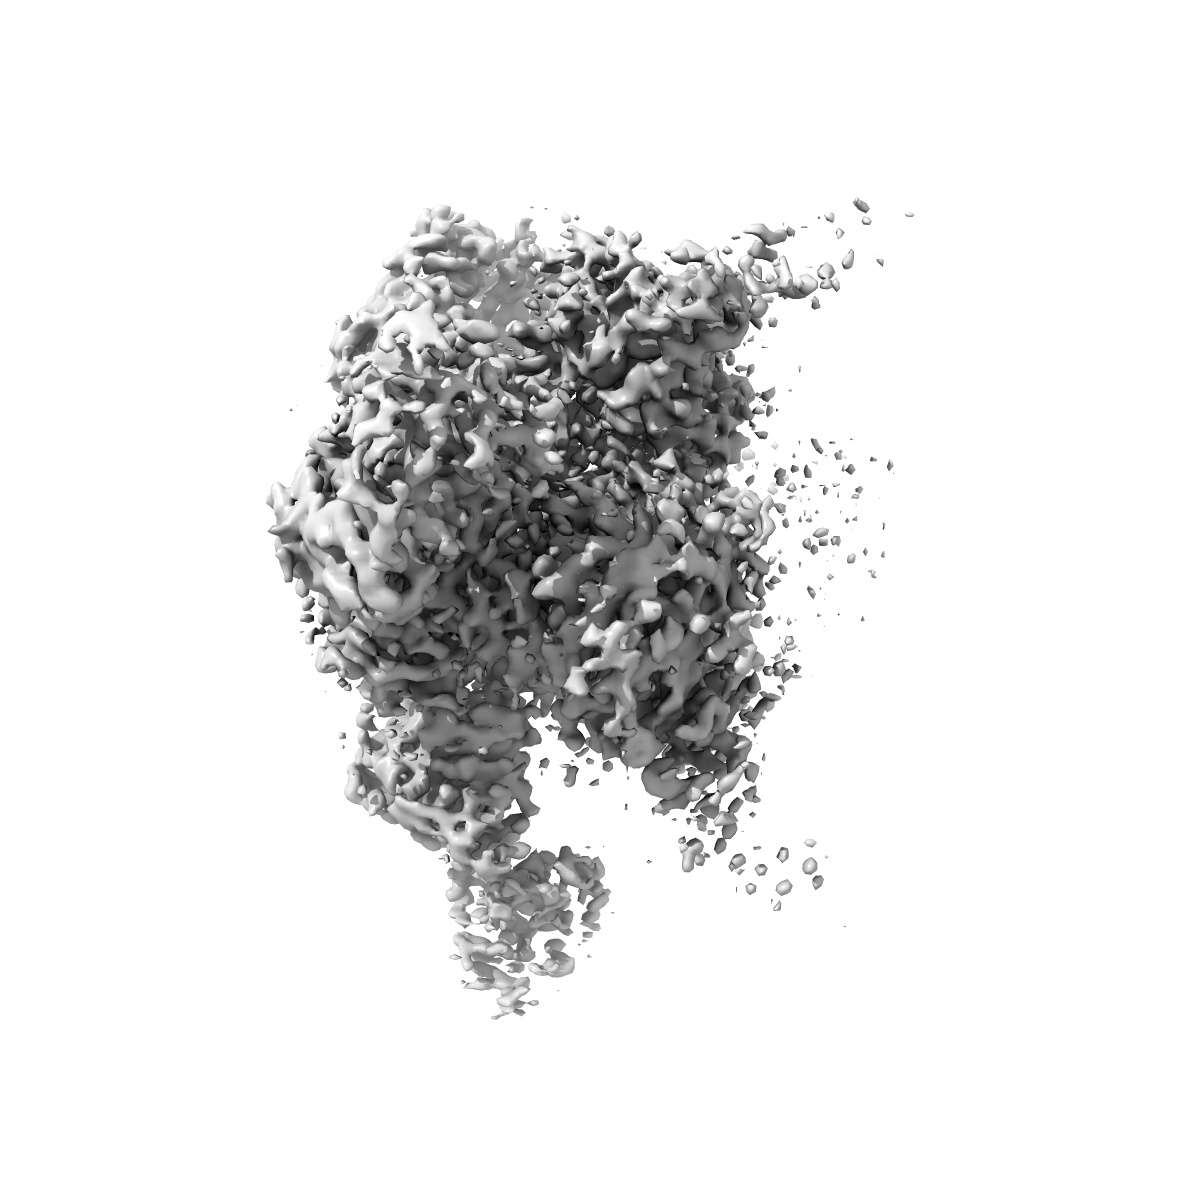

Cryo-EM structure of HIV-1 BG505 SOSIP.664 Env bound to 3-sCD4, 3-VRC34.01 Fab with one gp120 rotated, Population 4

Conformational trajectory of the HIV-1 fusion peptide during CD4-induced envelope opening.

Thakur B, Katte RH , Xu W , Janowska K, Sammour S, Henderson R , Lu M, Kwong PD , Acharya P

(2025) Nat Commun , 16 , 4595 - 4595